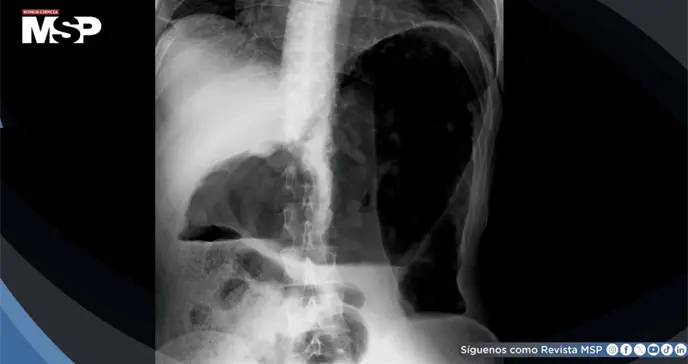

La radiografía simple de abdomen documentó dilatación colónica extensa con pérdida de las haustraciones normales, hallazgos consistentes con megacolon tóxico. Ante la sospecha de una emergencia quirúrgica abdominal con compromiso sistémico, se decidió ingreso hospitalario urgente para manejo intensivo.